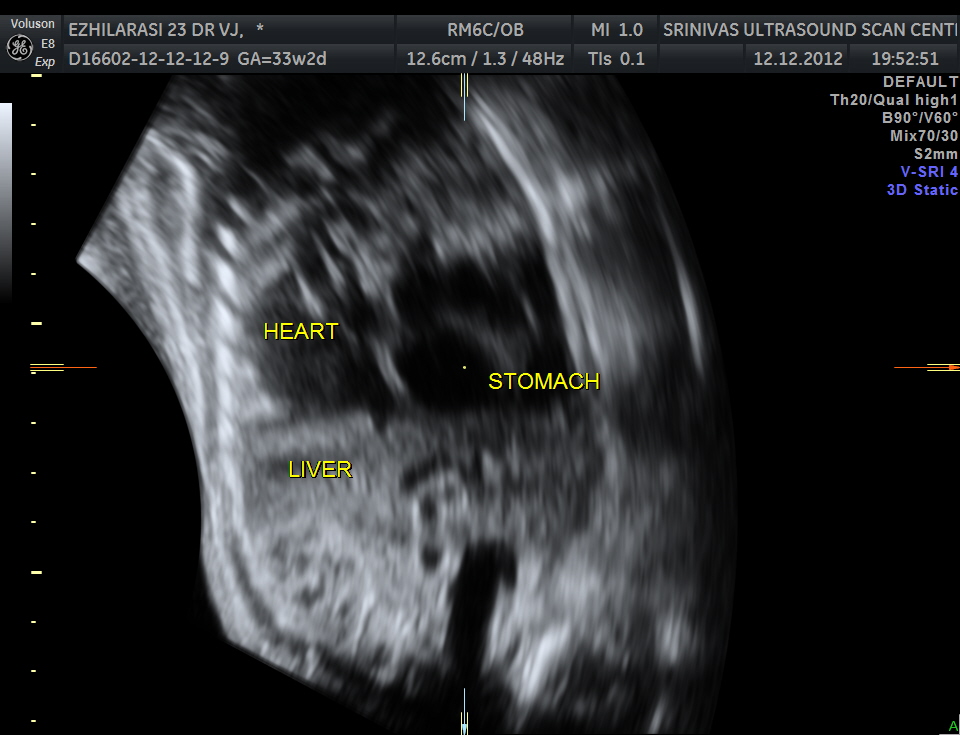

The heart was seen in the right side of thorax . The left hemithorax showed the stomach bubble and bowel loops suggestive of Congenital Diaphragmatic Hernia .